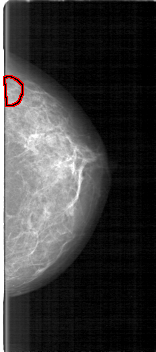

FILE: D_4119_1.LEFT_CC.OVERLAY

TOTAL_ABNORMALITIES 1

ABNORMALITY 1

LESION_TYPE CALCIFICATION TYPE FINE_LINEAR_BRANCHING DISTRIBUTION LINEAR

ASSESSMENT 3

SUBTLETY 3

PATHOLOGY MALIGNANT

TOTAL_OUTLINES 1

BOUNDARY

LEFT_CC LINES 5266 PIXELS_PER_LINE 2326 BITS_PER_PIXEL 12 RESOLUTION 43.5 OVERLAY